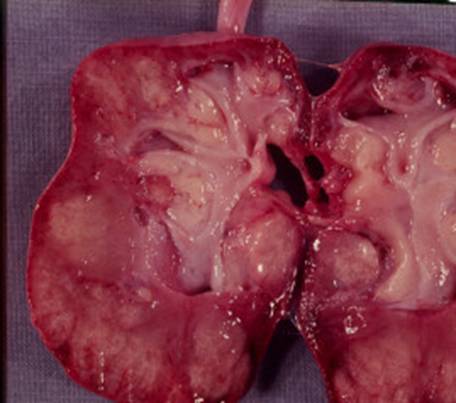

In formele cronice, rinichii sunt mici, atrofici cu cicatrici parenchimatoase care deformeaza suprafata renala, insotita de deformarea calicelor adiacente. Microscopic se observa o inflamatie acuta cu edem interstitial si infiltratie cu polimorfonucleare, neutrofile.

Pielonefrita cronica a rinichiului